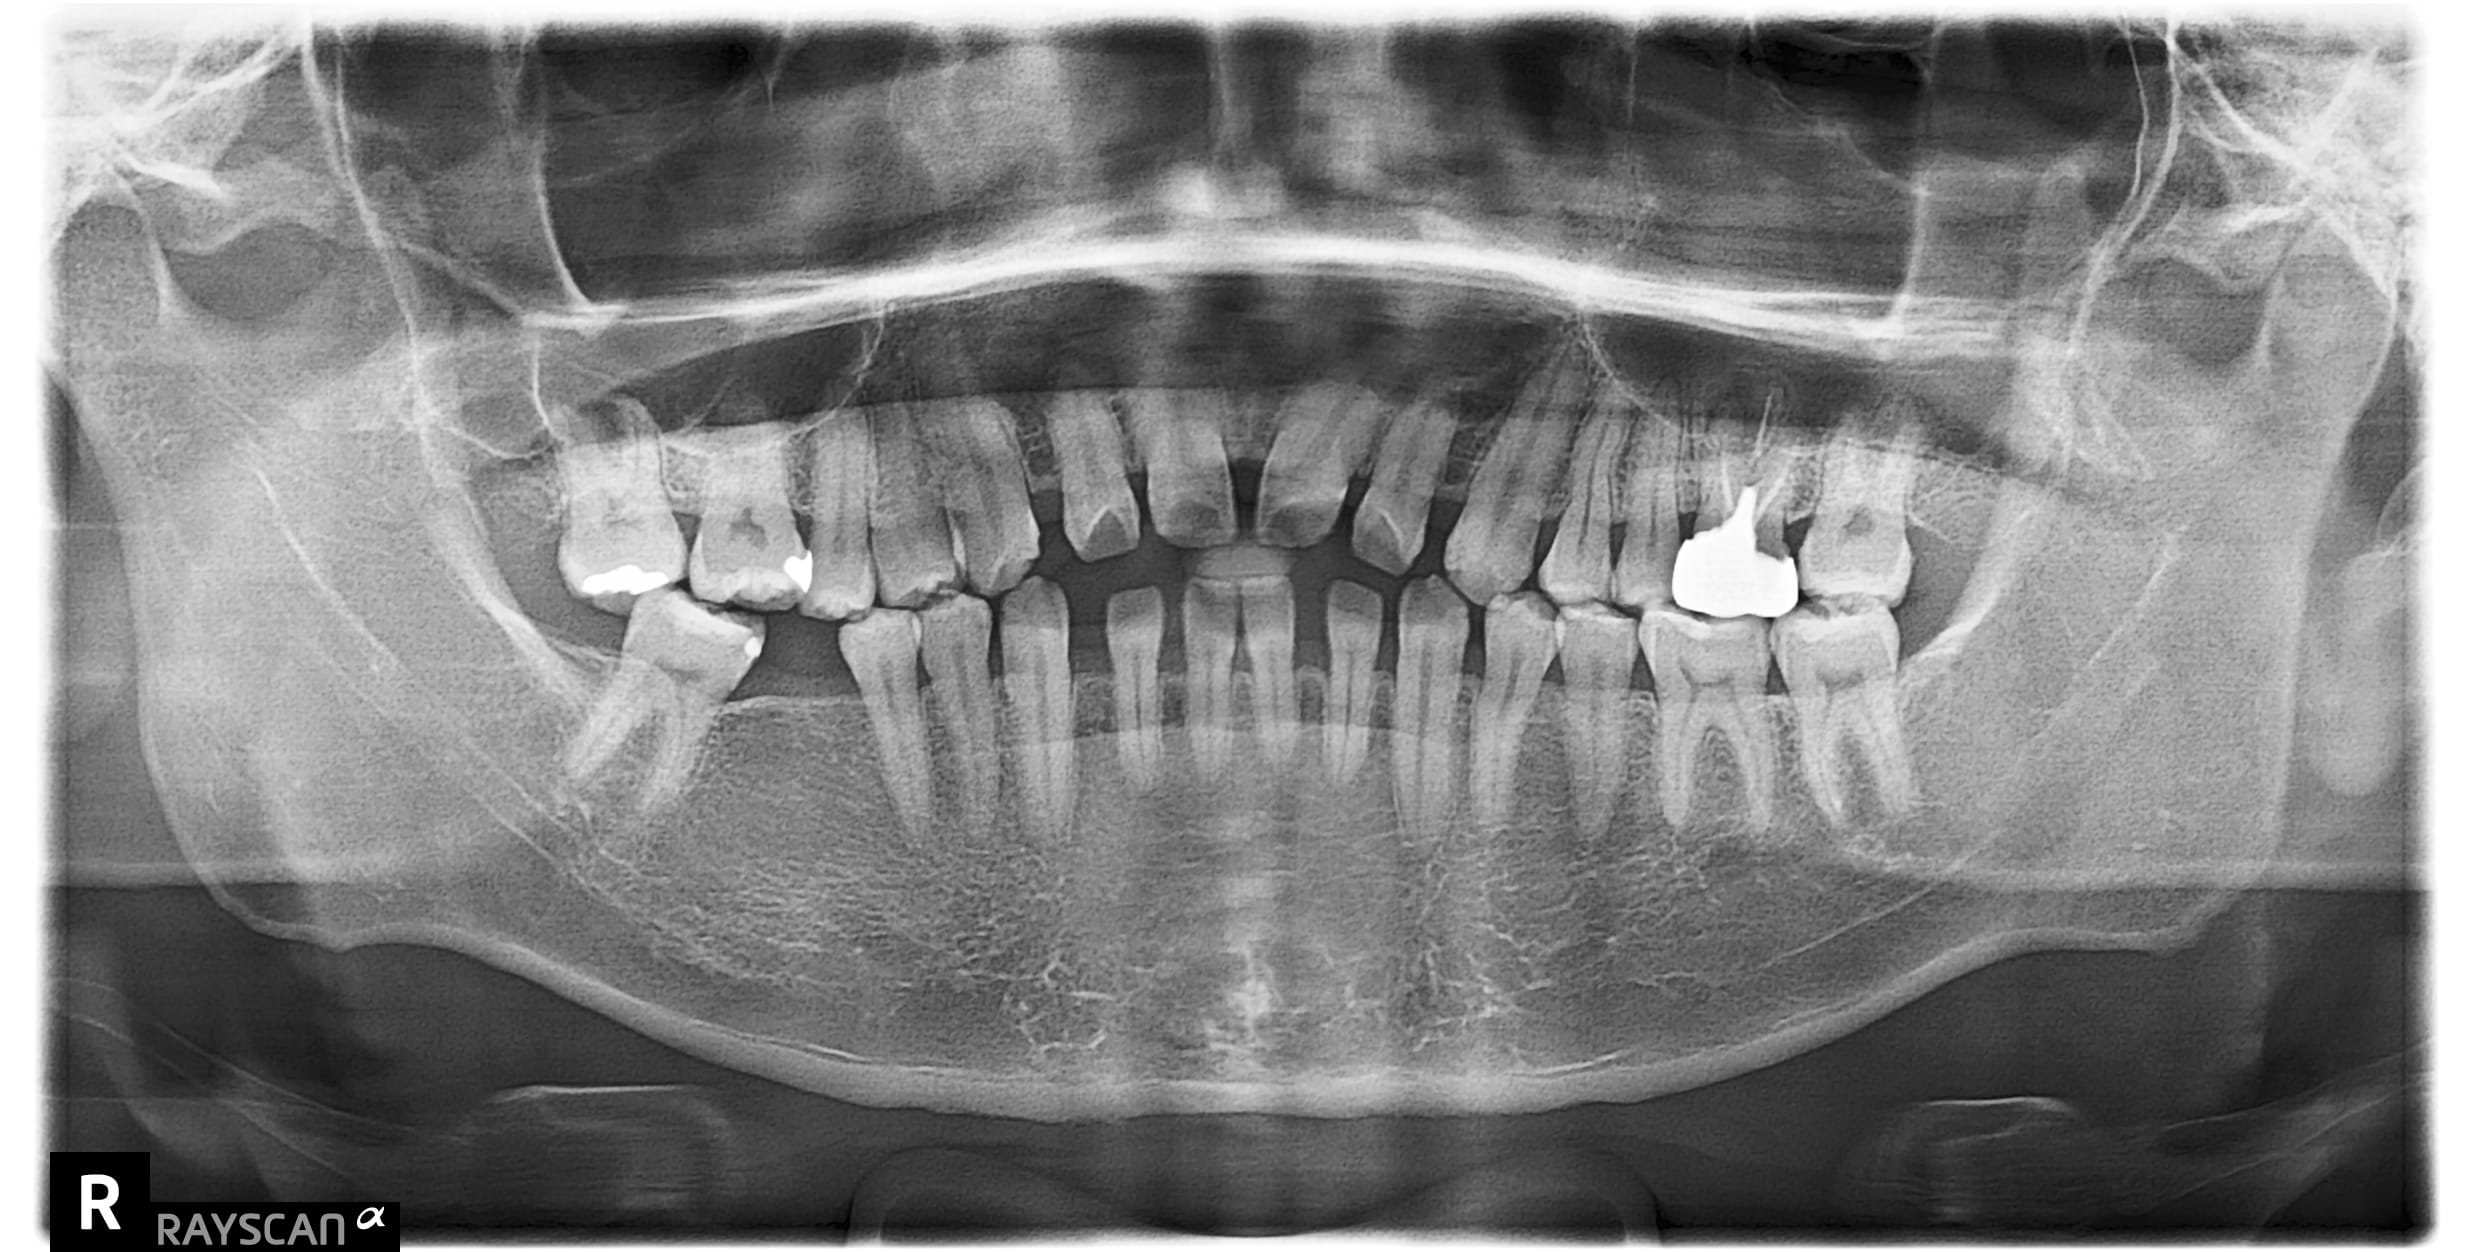

x先生左下第二小臼齒舊牙冠二次蛀牙斷掉,並影響到咬合問題 假牙不密合導致再蛀齒質脆弱咬東西斷,建議即

x先生左下第二小臼齒舊牙冠二次蛀牙斷掉,並影響到咬合問題 假牙不密合導致再蛀齒質脆弱咬東西斷,建議即

c先生因左上第一大臼齒根管後未裝牙套吃東西咬裂,故尋求協助治療。 牙齒裂致根部,需先拔除待傷口1-2

自述#46缺牙十年左右 想植牙改善右下第二大臼齒往前倒的狀況 骨頭狀況良好可直接植牙,等植牙接出後需